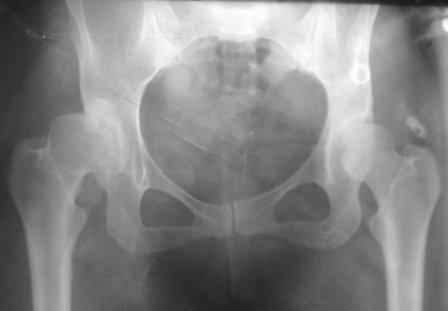

Типичная концовка проигнорированного диспластического состояния сустава. Дисплазия тазобедренного сустава часто встречающаяся патология у жителей Центральной Азии вследствие тугого пеленания в детстве. Традиционно ребенок находится в течение дня в так называемой кроватке "бешик", удобной в быту, но она впоследствии приводит к недоразвитию тазобедренного сустава.

Это первые признаки начала деструкции сустава, и возможно, аналгетики помогут для купирования болей, но в течение очень короткого времени от сустава ничего не останется, и в дальнейшем останется только артропластика.

При более сохранном суставе от дальнейшего разрушения можно было бы сохранить только периориентацией нагрузки на сустав - Периацетабулярной Остеотомией .

Данный сустав в начальной стадии разрушения, но все-таки я бы сделал обзорный таз и отдельные снимки сустава в 30 градусной абдукции и аддукции. Также снимки с внутренней и наружной ротацией для оценки состояния головки бедра.